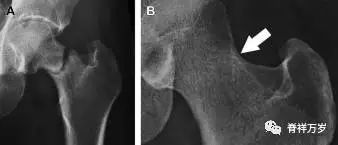

髋臼骨折

髋臼骨折最常见的类型是髋臼后壁骨折,几乎占髋关节骨折的 1/4,且常常合并髋关节后脱位。由于骨性结构重叠,可能肉眼看上去觉得非常轻微的骨折,事实却并非如此。髋臼后缘中断常常是髋臼后壁骨折的一个特征(图 1)。

图 1 为髋臼后壁骨折伴髋关节脱位患者。A 右侧髋关节 X 线片示股骨头后方可见一骨折线(箭头),髋臼后缘中断。B 左侧髋关节 X 片对照可见髋臼后缘连续(箭头)。C CT 三维重建图像示髋臼后壁缺损,可见旋转、移位的骨折块(箭头)